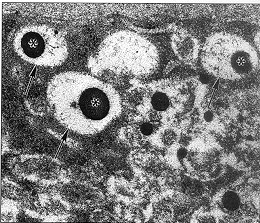

图8 内皮有大量的无界膜包涵物(箭号)内含有淡染色的原纤维粒物质和电子反差强的小体(星号)(×60000)